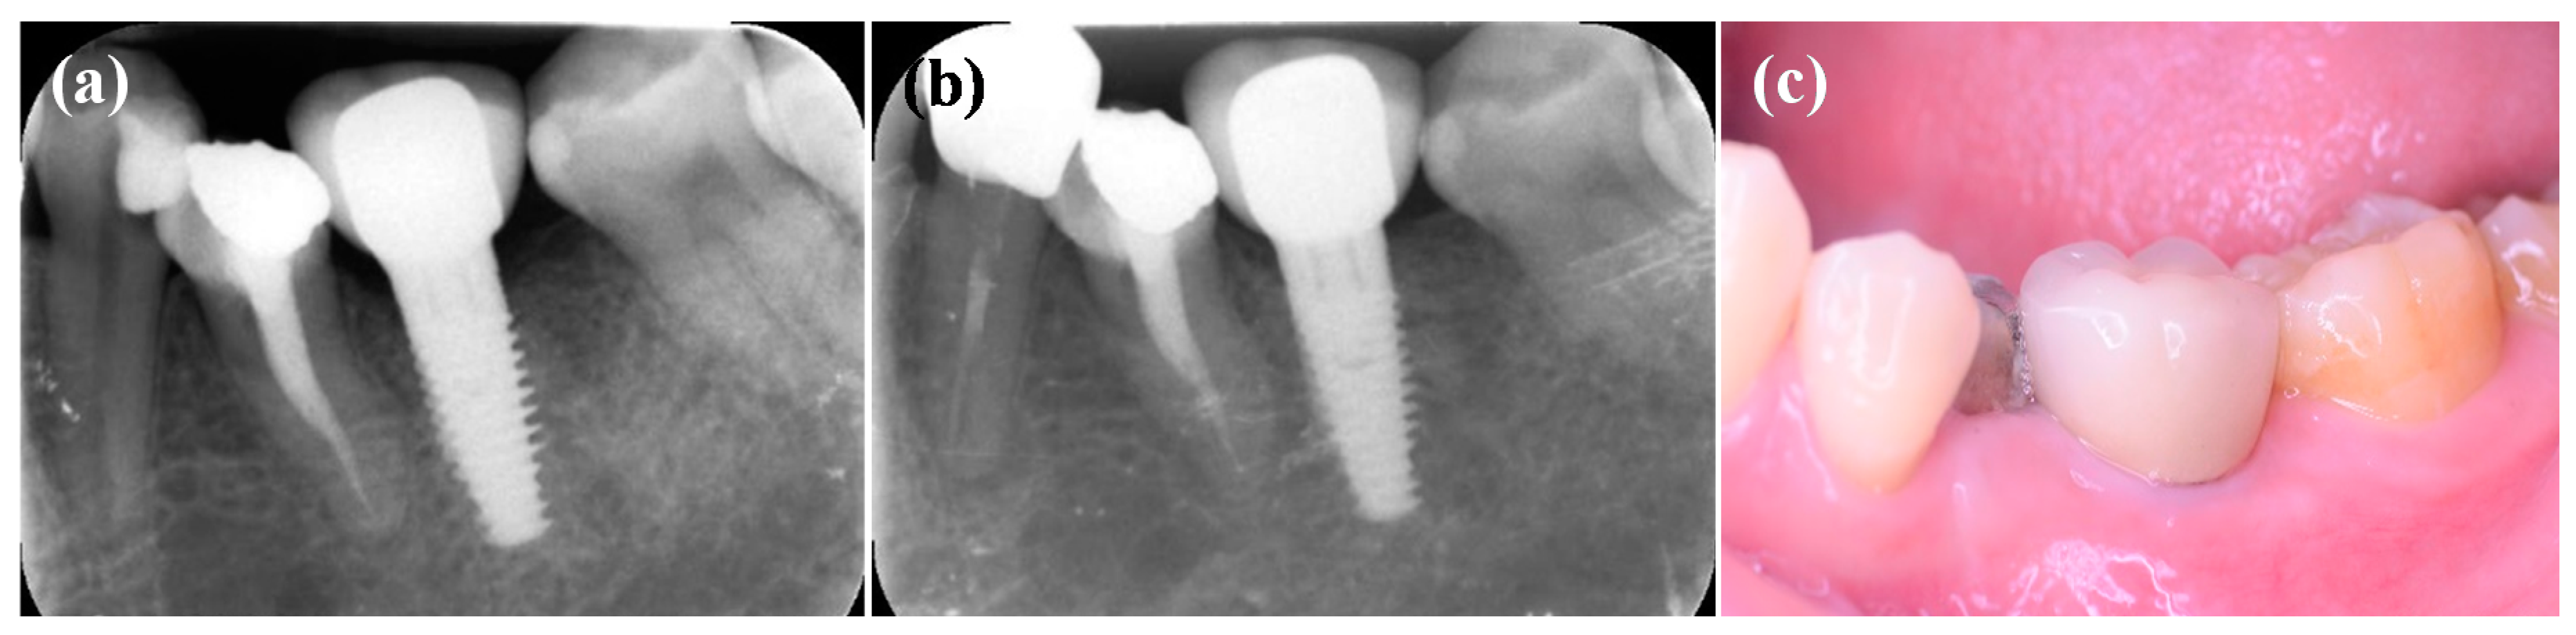

3.4. Clinical Evaluations of the IDCT-Modified Ti Implant